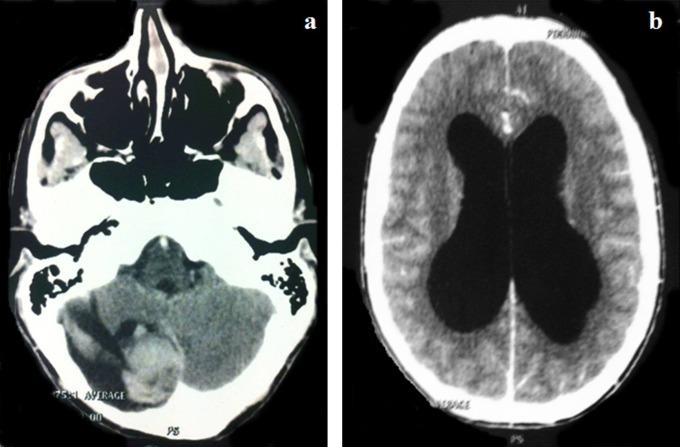

Pilocytic astrocytoma is a slowly growing neoplasia that represents the most frequent cerebral tumor in pediatric age. Malignant transformation is rare and it is usually related to previous radiotherapy. The authors describe a case of a spontaneous malignant transformation of a pilocytic astrocytoma. A 3-year-old boy was diagnosed with a cerebellar hemisphere tumor. He was submitted to a complete excision of the lesion, and histological findings were consistent with pilocytic astrocytoma. It was negative for p53. Twelve years later he presented with a local recurrence. Histopathological diagnosis was glioblastoma and it was positive for p53. Death from disease progression occurred 16 months after the diagnosis of glioblastoma. This case suggests that patients with pilocytic astrocytoma need closer follow-up and further genotypic studies in order to provide clues to clinical behavior. Such understanding can allow us to stratify treatment accordingly and to proceed to more aggressive treatment when necessary.

毛细胞型星形细胞瘤是一种生长缓慢的肿瘤,是儿童期最常见的脑肿瘤。恶性转化罕见,通常与先前的放疗有关。作者描述了一例毛细胞型星形细胞瘤自发恶性转化的病例。一名3岁男孩被诊断为小脑半球肿瘤。他接受了病变的完全切除,组织学检查结果符合毛细胞型星形细胞瘤。p53检测为阴性。12年后,他出现局部复发。组织病理学诊断为胶质母细胞瘤,p53检测为阳性。胶质母细胞瘤诊断16个月后,患者因疾病进展死亡。该病例表明,毛细胞型星形细胞瘤患者需要更密切的随访和进一步的基因分型研究,以便为临床行为提供线索。这样的了解可以使我们据此对治疗进行分层,并在必要时采取更积极的治疗措施。